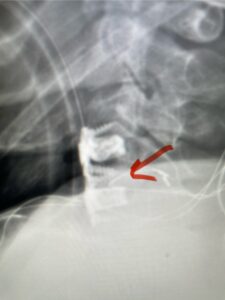

Fig 1: Sagittal cervical CT myelogram demonstrating spinal cord compression at C2-3 above the prior anterior cervical fusion (red arrow)